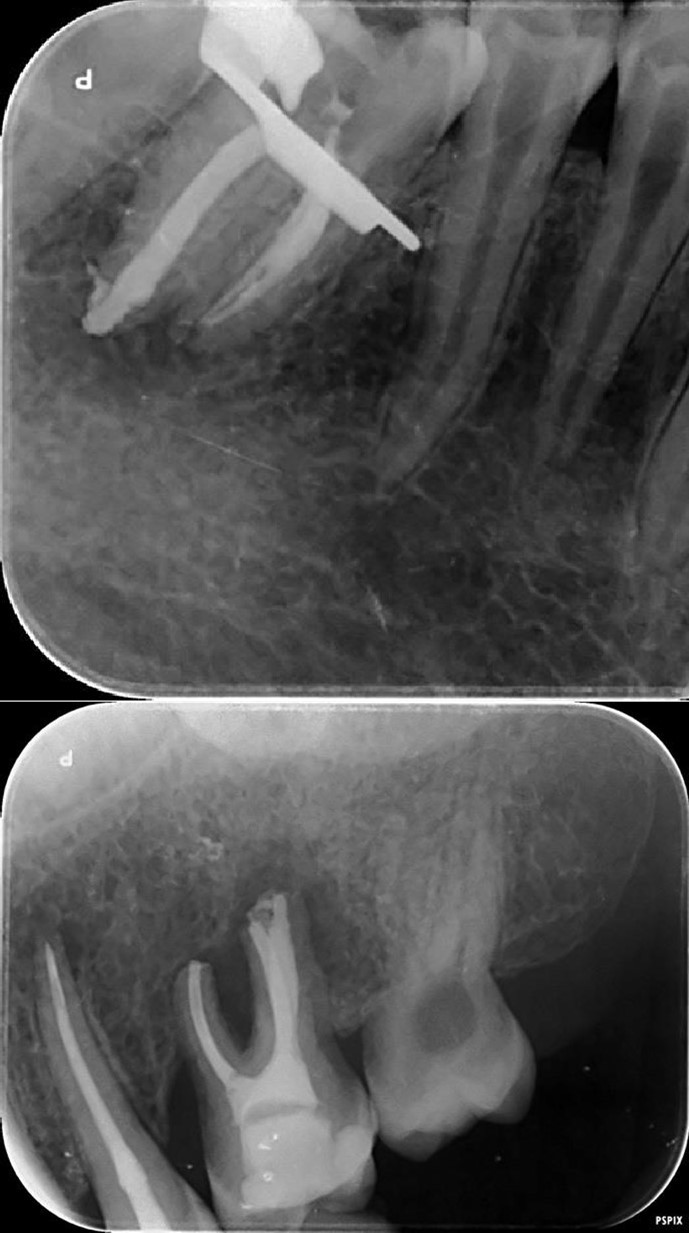

3. Endodontic root canal treatment and retreatment were performed on teeth 14, 15, 16, 25, 26, 35, 36, and 46 using a K manual file 10/30/40/50/60/70 (Dentsply-Maillefer). Hyflex Edm (Coltene) 25/06 was used for the preparation of the canals, which were irrigated with 3% sodium hypochlorite and 17% ethylenediaminetetraacetic acid. Gutta-percha were calibrated to the diameter of the root apex constriction and obturation was conducted using Endosequence Bc Sealer (Brasseler) 15.

Complete healing of periapical lesions and treatment of teeth 26 and 16 with advanced endo-perio lesions posed challenges due to the patient’s delayed supplementation. In this case, surgical endodontic procedures and the extraction of teeth with advanced endo-perio lesions were considered risky because of the underlying metabolic healing impairment. Figure 3

Figure 3.6. 7, 8, 9, and 10 showing postoperative periapical radiographs of these endodontic treatments.